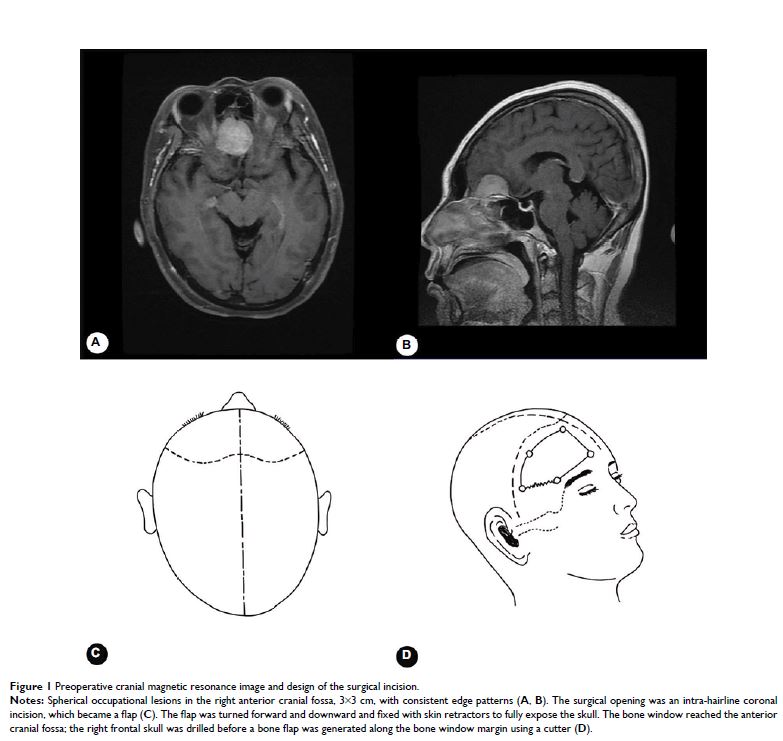

- 作者:Xiong Xiao, Hao Ren, Nan Ji, Fang Luo

- 期刊:Journal of Pain Research